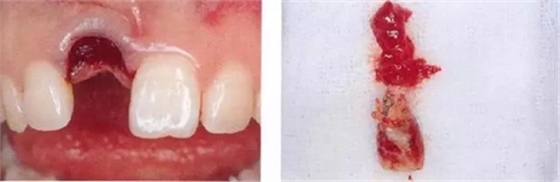

▲圖44-4,5

圖44-6

圖44-4~6 拔牙后通過骨移植材以及結(jié)締組織移植(CTG)進行GBR。